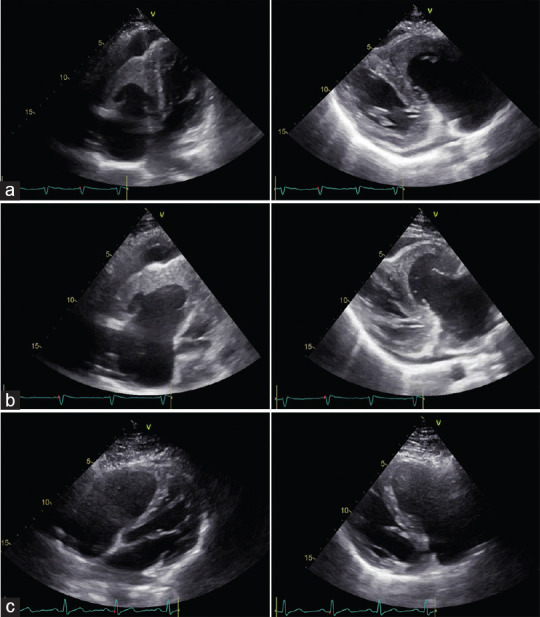

Hypereosinophilic syndrome (HES) is a systemic disorder with various manifestations, characterized by hypereosinophilia and caused by primary or secondary conditions. Loeffler's endocarditis (LE) represents a frequent cardiac manifestation of HES, caused by infiltration of the myocardium by eosinophilic cells, which determines endocardial damage, with subsequent inflammation, thrombosis, and fibrosis of either one or both ventricles. The diagnosis of cardiac involvement is based on a multimodality approach (i.e., two-dimensional transthoracic echocardiography [2D-TTE], speckle-tracking echocardiography [STE], and cardiac magnetic resonance [CMR]), with different findings depending on the stage of disease. STE may be useful in the initial phase when traditional imaging techniques may result negative, whereas CMR allows myocardial tissue characterization along with a better definition of the right ventricle. We present a rare case of LE with isolated right ventricular involvement in a patient with HES caused by chronic eosinophilic leukemia with constitutively activated fusion tyrosine kinase on chromosome 4q12, successfully treated with imatinib mesylate.